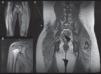

The 5 patients had proximal muscle weakness, elevated levels of 1 or more muscle enzymes (alanine aminotransferase, aspartate aminotransferase, creatine kinase, aldolase), and muscle MRI findings consistent with myositis in the upper and lower limbs (Fig. 1). The electromyogram, performed in 4 patients, showed a myogenic pattern in the biceps and/or quadriceps. Two patients had positive antinuclear antibodies with low titers (1/160). None of the patients underwent muscle biopsy and a skin biopsy was performed in all cases (Table 1).

Magnetic resonance imaging (MRI) findings. A, Patient #1. Whole-body muscle MRI. Increased intensity in STIR (short tau inversion recovery) sequence of buttock region and vastus lateralis, consistent with muscle edema, a sign of muscle inflammation. Integration of this finding confirmed the diagnosis of juvenile dermatomyositis. B, Patient #4. MRI of shoulder muscle. Increased signal from right deltoids and fascia in association with a small quantity of liquid in the subacromial bursa. C, patient #5. Whole-body muscle MRI after initiation of treatment. Note the hypointense calcinosis cutis plaque in the right low lumbar region (*).